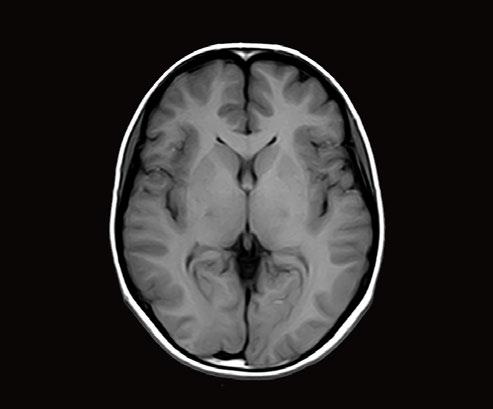

Fig 1: Next generation MRI is being used to gather data on brain tissue volumes Dr. Steve McNally

From this season at Manchester United Football Club, we have started to gather data by using MRI (see fig 1) to measure volumes of brain tissue in specific areas, to monitor for a decrease in volumes over time. If the volumes become unusual or deviate from the norms that we would expect, it may help us identify early changes of CTE that need closer monitoring. This is a new, long-term data gathering study in our cohort of players that has been facilitated with the new next generation MRI3 now in place at our medical centre.

MRI is also an excellent choice of tool for the diagnosing and monitoring of Chronic Traumatic Encephalopathy (CTE), the result of repetitive brain trauma from blows to the head and repeated episodes of concussion, which in football may have come from player contact or heading the ball. It is a hot topic in all contact sports such as boxing, rugby and martial arts and follows research at the University of California, Los Angeles (UCLA) using MRI as the option to explore CTE without any dose implications to patients2